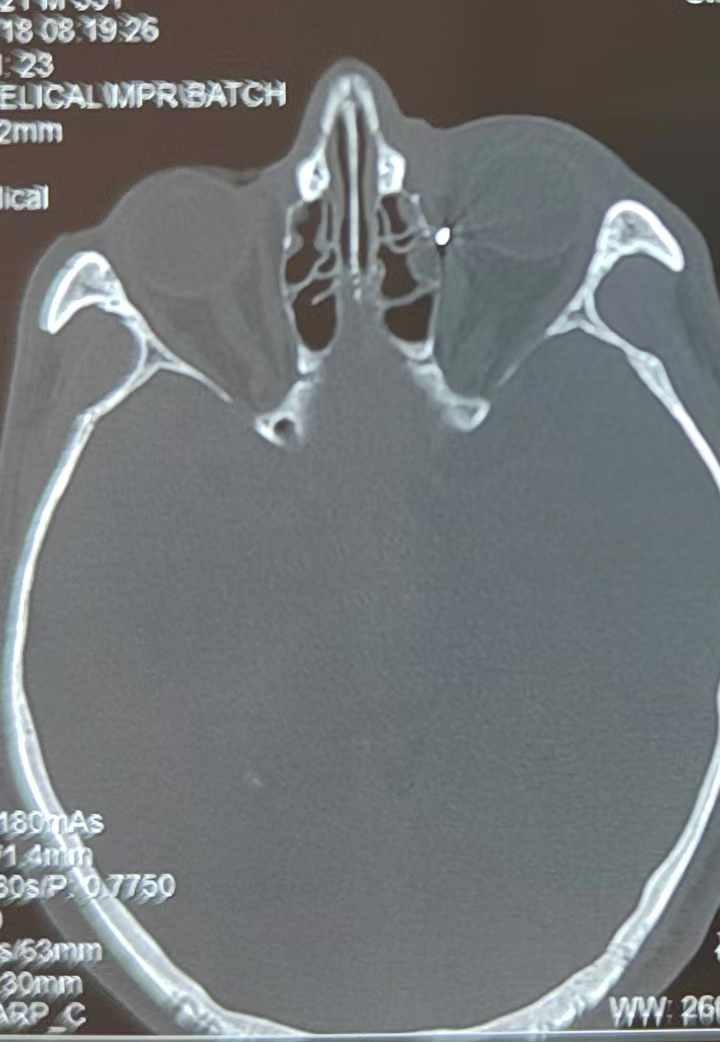

從CT報(bào)告中可以看出,高先生眼內(nèi)的異物不是很大,但位于眼窩深處,緊鄰鼻骨,從CT影像判斷應(yīng)該是金屬或合金異物。一般臨床上遇到這樣的情況,醫(yī)生會建議“保守觀察”,若異物傷及神經(jīng)、發(fā)生炎癥感染等,則需到條件較好、有眼眶病和眼外傷專業(yè)醫(yī)師的醫(yī)院進(jìn)行二期眶內(nèi)異物取出術(shù)(2021年《中國眼眶異物診斷和治療專家共識》)。

李海波博士介紹,眶內(nèi)異物想要通過手術(shù)取出,難度很大,一是因?yàn)槲恢秒[匿,無法實(shí)現(xiàn)可視化操作;二是如果是磁性異物,現(xiàn)有手術(shù)工具磁性強(qiáng)度有限,很難吸出這么深的異物;三是可操作空間極為狹小,眶周軟組織多,異物周邊包裹緊密,像高先生這種情況,異物周邊還有很多神經(jīng)、血管,手術(shù)難度更高。